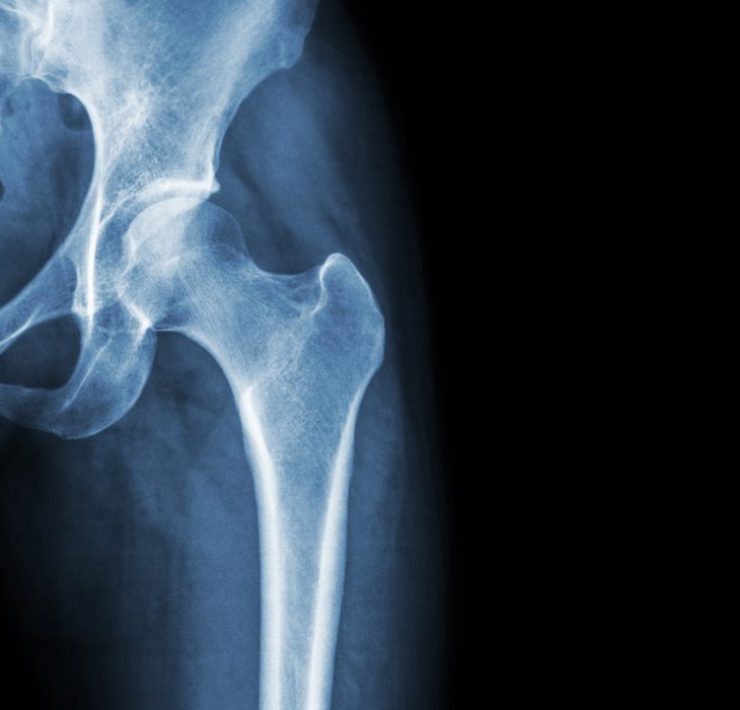

Busting Myths and Misconceptions about Osteoporosis

One in two women over the age of 50 will suffer a fracture caused by osteoporosis in her remaining lifetime. Despite its prevalence, there are many myths and misconceptions about this “silent” disease. These myths may be a reason why osteoporosis is underdiagnosed and undertreated.

Truth: Osteoporosis often affects women after menopause. Natural menopause can occur as early as age 50. The rate of bone loss after menopause is increased with the accompanying loss of estrogen. Osteoporosis is a progressive disease that lowers the density of bones over time, making them weaker and more likely to fracture.